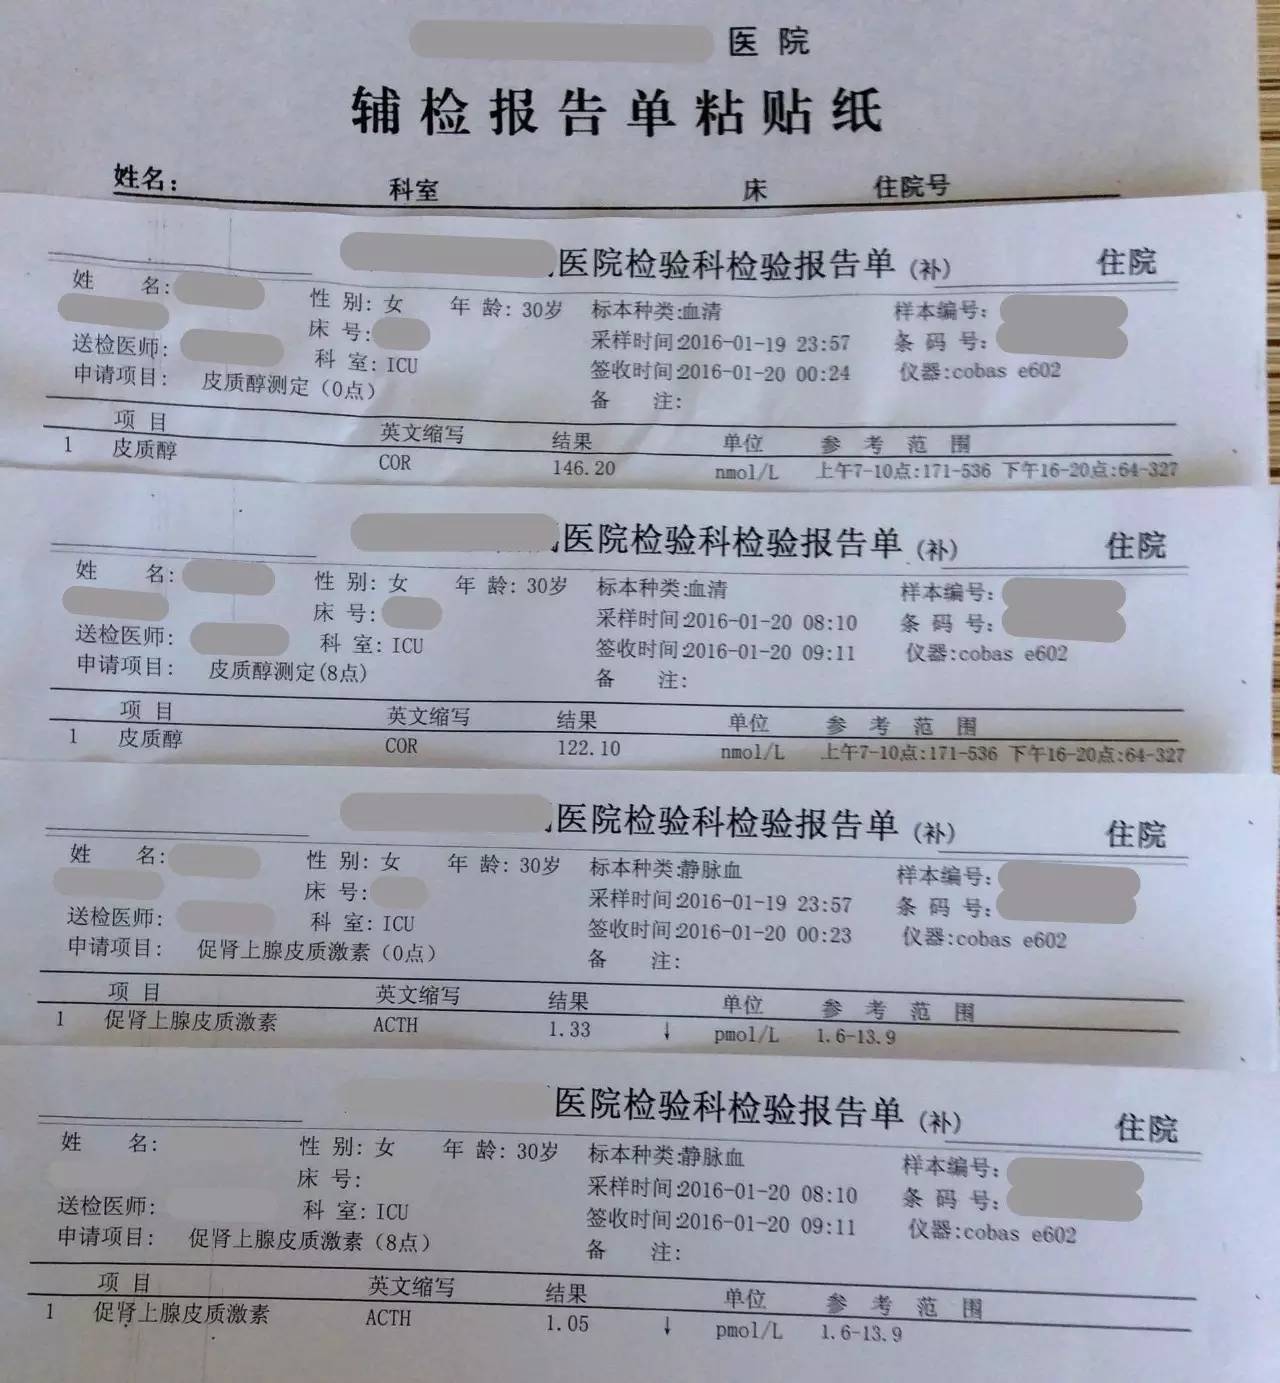

目前患者面临的问题是出现了甲状腺功能减退症和肾上腺激素需要减量的问题。结合患者产后一系列的意外和抢救过程,要警惕患者出现Sheehan syndrome(希恩综合征),因为低血压、出血等等引起垂体缺血缺氧所致。

2.患者应用甲强龙,当时是因为出现了休克为了抢救所用,目前情况明细好转,可以每周(也就是贵院内分泌大夫会诊的7~10天)减量甲强龙1片(4mg); 但因为患者可能存在继发性肾上腺皮质功能减退症(继发于希恩综合征),减量到全天2片时需要评估清晨未服药前ACTH和血皮质醇、电解质、性腺激素六项来评估是否能够完全停药,还是需要减成替代剂量,此时可以应用泼尼松来替代甲强龙,泼尼松一片是5mg,等效于甲强龙1片,4mg,如果确实出现肾上腺皮质功能减退,可以逐渐减量到泼尼松全天1片(2.5mg,早上和下午各服用一片)。到时候再根据患者复查的情况判断肾上腺功能的恢复情况。